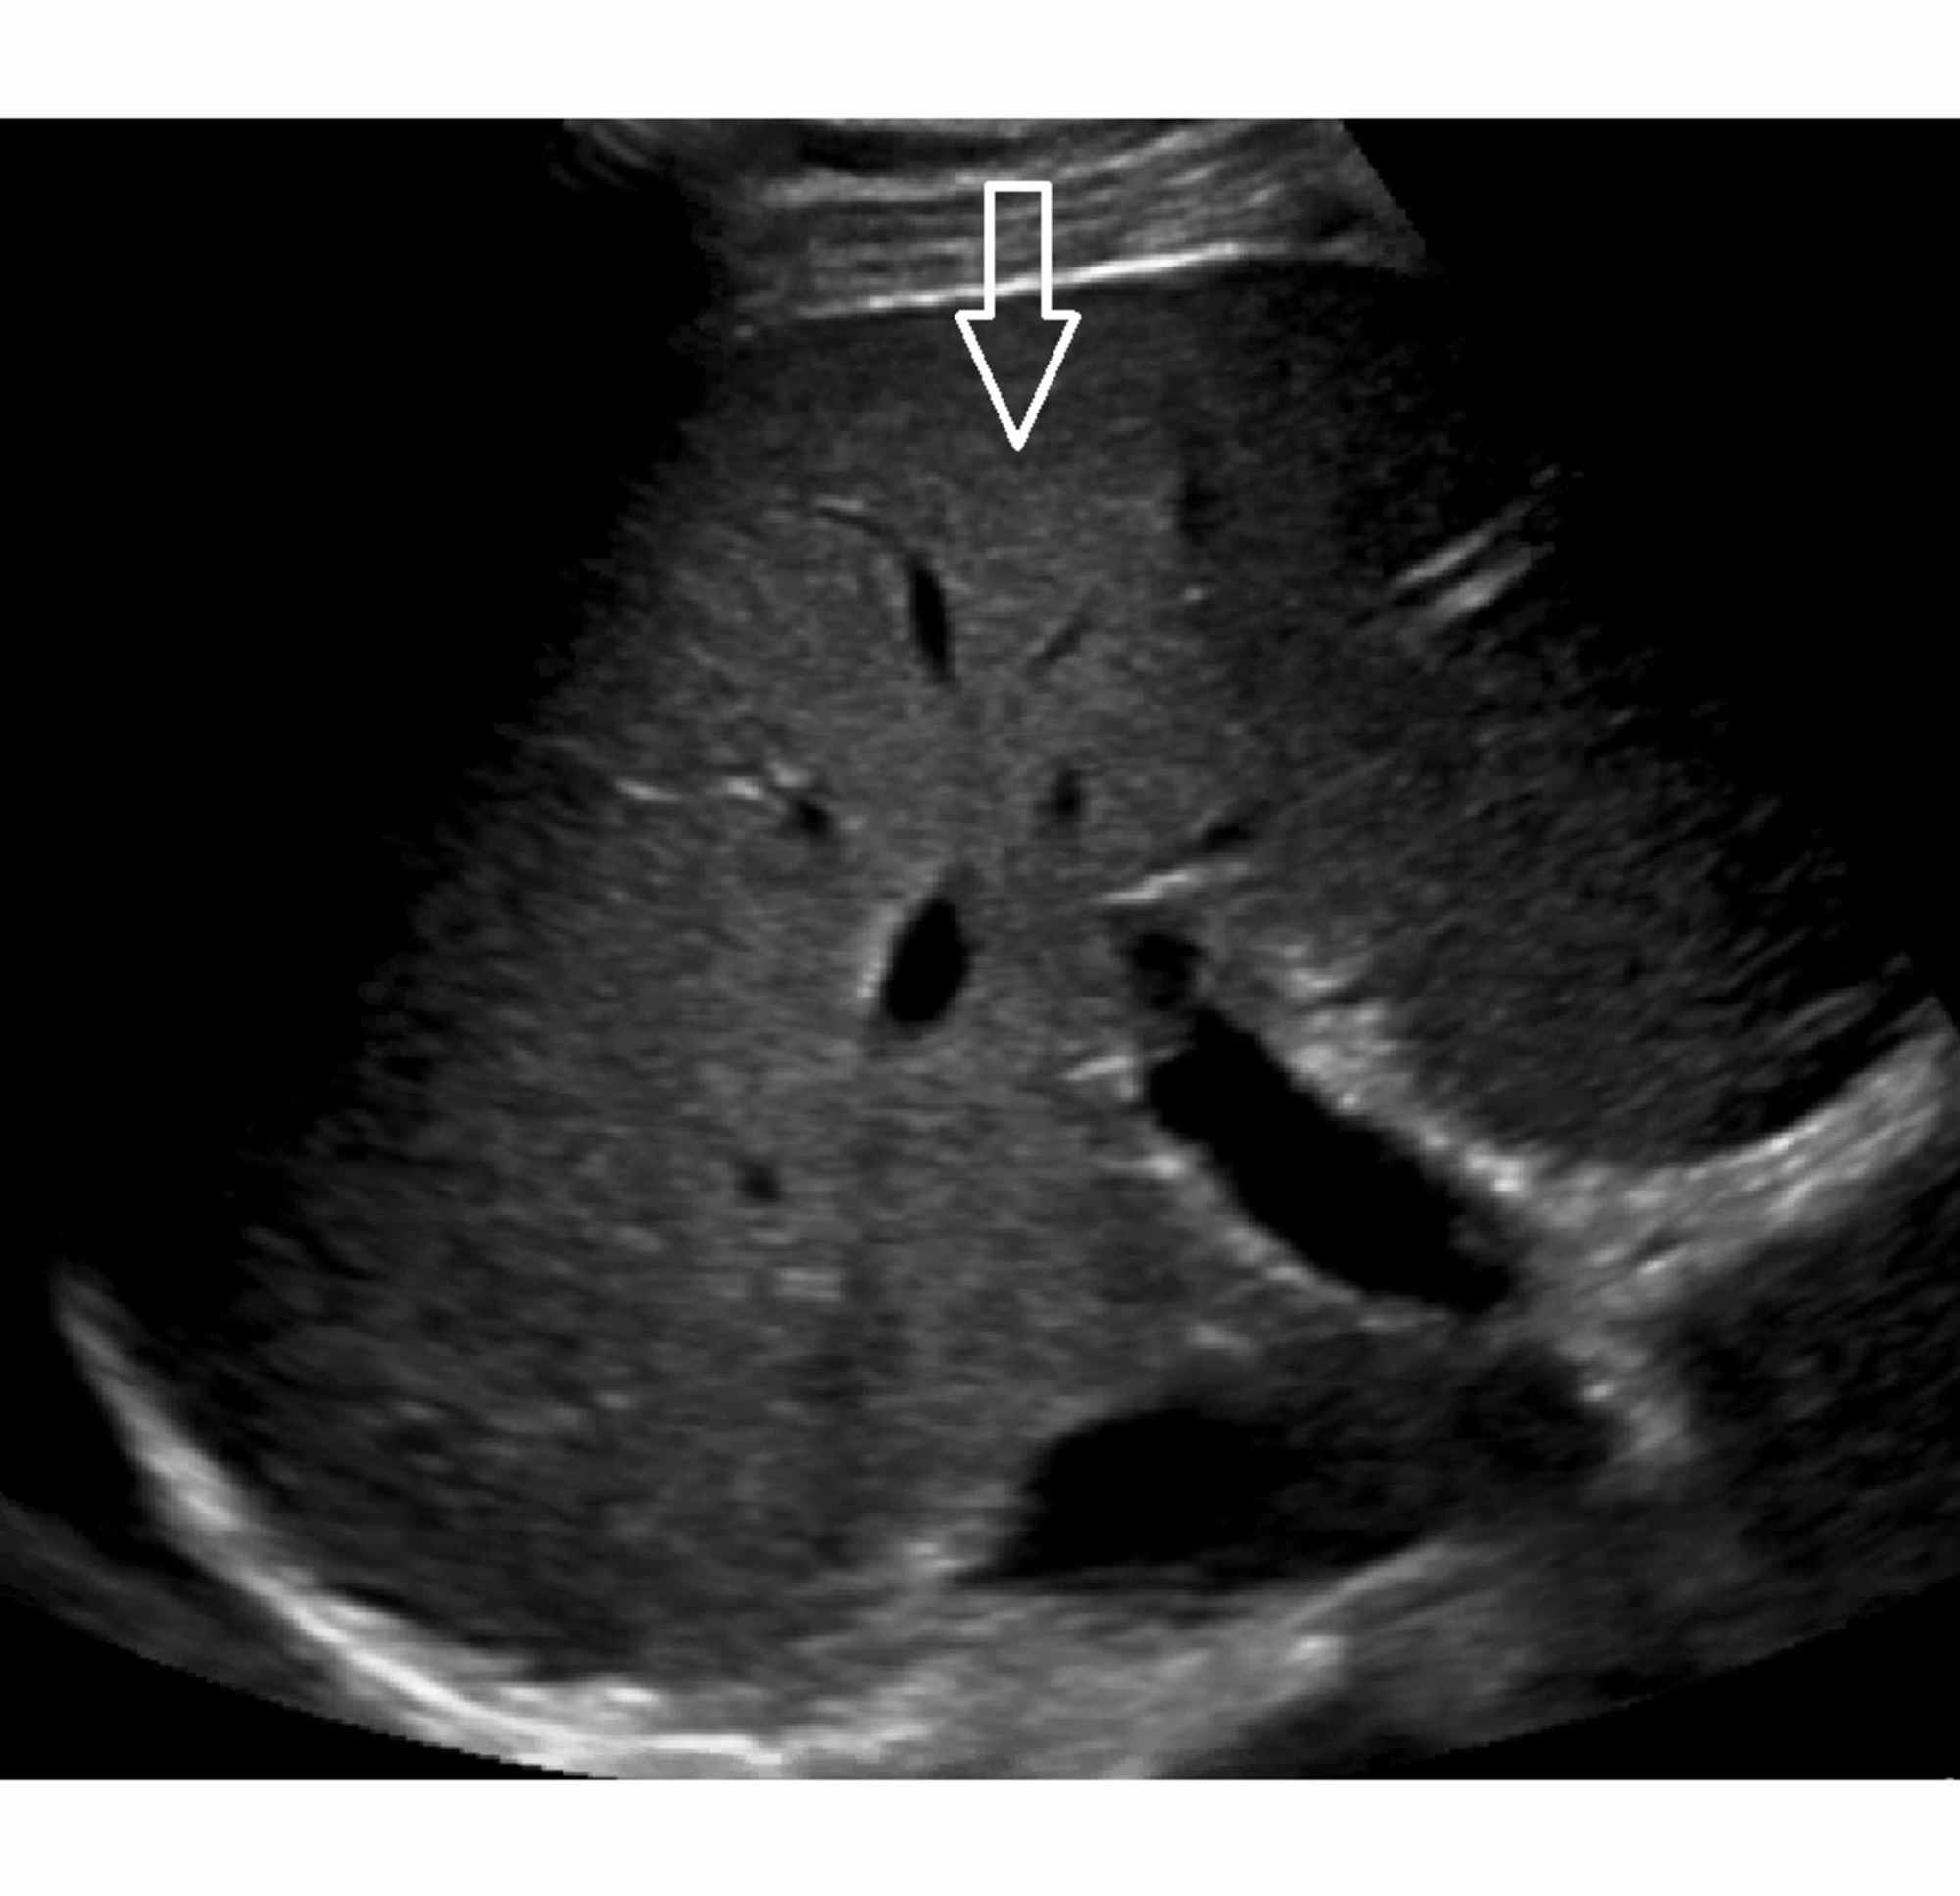

Non-invasive evaluation of liver cirrhosis using ultrasound – Clinical …

Non-invasive evaluation of liver cirrhosis using ultrasound – Clinical …

Ultrasound Image of Liver Cirrhosis Stock Photo – Image of healthcare …

Cirrhosis echocardiography or ultrasound – wikidoc